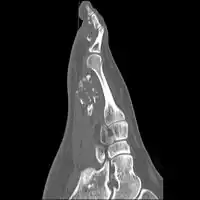

Medical imaging usually shows a well-defined wide-based bony growth on the surface of bone.[5] It can be pedunculated and irregular, giving it a "bizarre" appearance, and is not connected to underlying bone.[2]

X-ray left foot: Bizarre parosteal osteochondromatous proliferation in 2nd toe -